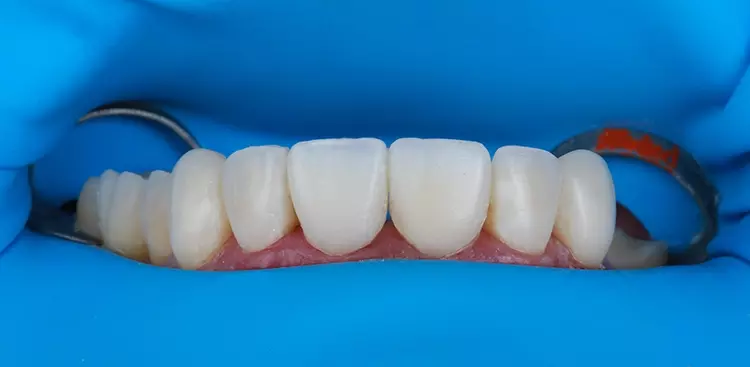

Das für das Mock-up verwendete Material bestand aus selbsthärtendem Mikro-Hybrid-Komposit für provisorische Kronen und Brücken (Structur 2, VOCO). Das thermoviskose VisCalor bulk (VOCO) wurde additiv in einen weiteren Silikonschlüssel injiziert, um die okklusalen Aspekte zahlreicher OK-Zähne sowie der rechten unteren Prämolaren und Molaren des Unterkiefers direkt im Mund zu rekonstruieren. Die Eckzahnführung wurde hingegen mit Admira Fusion (VOCO) wiederhergestellt.

So wurde die Rehabilitation zur Wiederherstellung von okklusaler Stabilität, VDO (Vertikale Dimension der Okklusion) und funktionsorientierten Zahnführungen Schritt für Schritt vorgenommen. Zwischenzeitlich visualisierte der Zahntechniker die vorläufige Implantatplanung für die später folgende navigierte Implantation (Abb. 10). Der chirurgische Eingriff wurde simuliert, indem virtuelle Zähne in der CAD-Planungssoftware (Implant Studio, 3shape) entworfen wurden, wobei die Kontur des Alveolarfortsatzes beibehalten wurde.

Das Ergebnis entsprach den Erwartungen des Patienten. In der Nachbehandlungsphase wurde die Okklusion erfolgreich wiederhergestellt, wobei eine neue vertikale Dimension, eine passende Kronenform und -größe sowie funktionsorientierte Okklusionsebenen erreicht wurden.

Es konnten sofortige positive ästhetische und funktionelle Verbesserungen beobachtet werden, die auch 6 Monate nach Eingliederung noch deutlich sichtbar sind. Darüber hinaus wurden okklusale Stabilität und korrekte Zahnführungen erreicht.